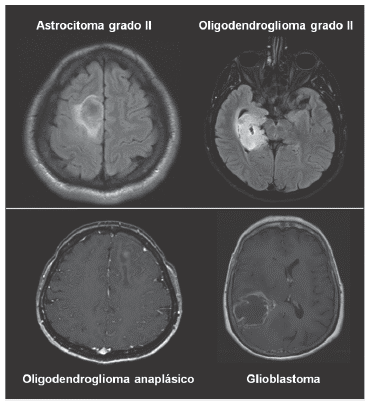

Se incluyeron 42 pacientes (edad promedio 41 años) con diagnóstico de glioma difuso. Mediante la clasificación de tumores del sistema nervioso central de la OMS, versión 2007 11, se reportaron 15 gliomas grado II (7 astrocito-mas, 4 oligodendrogliomas, 2 gliomas mixtos, 2 gliomas no especificados) y 27 gliomas de alto grado (14 glioblastoma, 8 astrocitoma III, 3 oligodendroglioma anaplásicos, 2 gliomas mixtos anaplásicos) (tabla 1) (figura 1).

Imagénes de resonancia magnética cerebral de casos ilustrativos de diferentes tipos de gliomas cerebrales. Panel superior: secuencias T2-Flair ilustrando el aspecto radiológico de gliomas difusos de bajo grado. Panel inferior secuencias T1-gadolinio de pacientes con gliomas de alto grado.

Figura 1: Imagénes de resonancia magnética cerebral de casos ilustrativos de diferentes tipos de gliomas cerebrales. Panel superior: secuencias T2-Flair ilustrando el aspecto radiológico de gliomas difusos de bajo grado. Panel inferior secuencias T1-gadolinio de pacientes con gliomas de alto grado.